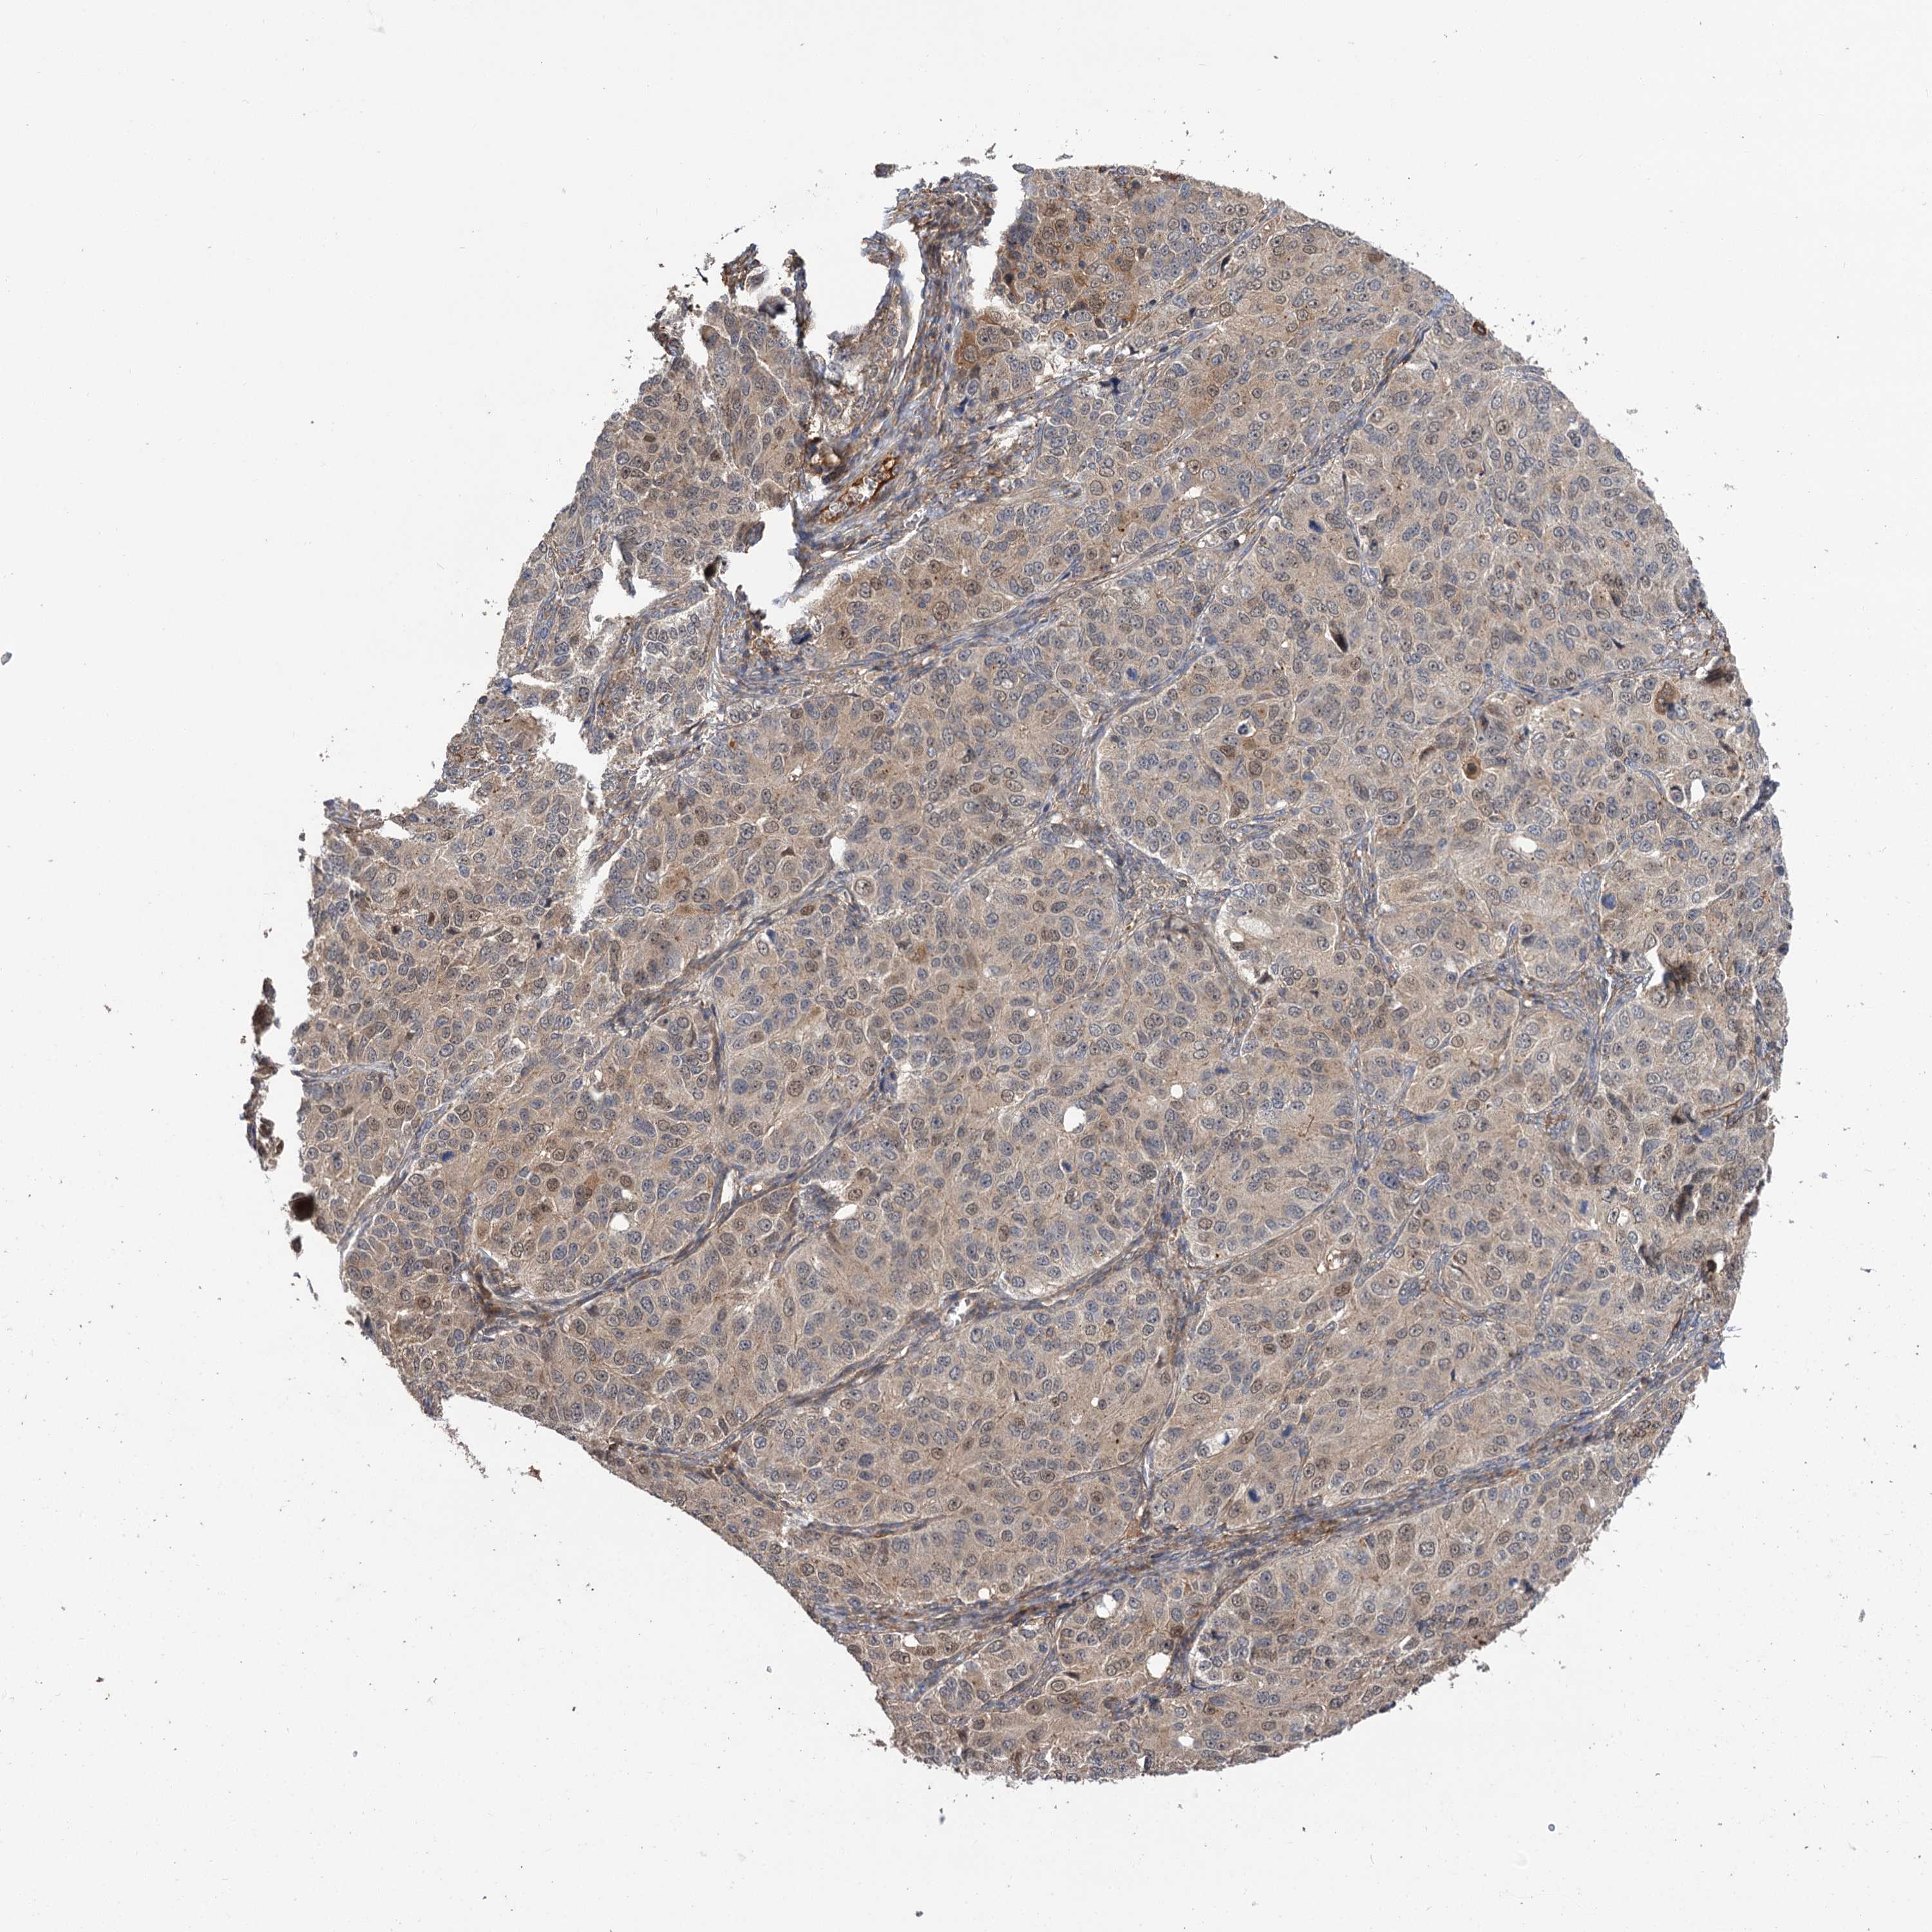

OVARIAN CANCER - Protein expressioni

A mouse-over function shows sample information and annotation data. Click on an image to view it in a full screen mode. Samples can be filtered based on level of antibody staining by selecting one or several of the following categories: high, medium, low and not detected. The assay and annotation is described here.

Note that samples used for immunohistochemistry by the Human Protein Atlas do not correspond to samples in the TCGA dataset.

Antibody stainingi

Antibody staining in the annotated cell types in the current human tissue is reported as not detected, low, medium, or high, based on conventional immunohistochemistry profiling in selected tissues. This score is based on the combination of the staining intensity and fraction of stained cells.

Each image is clickable and will lead to virtual microscopy that enables deeper exploration of all samples and also displays staining intensity scores, fraction scores and subcellular localization as well as patient and tissue information for each sample.

Antibody HPA038850

Antibody HPA038851

Cystadenocarcinoma, serous, NOS

Carcinoma, endometroid

Cystadenocarcinoma, mucinous, NOS

Carcinoma, NOS